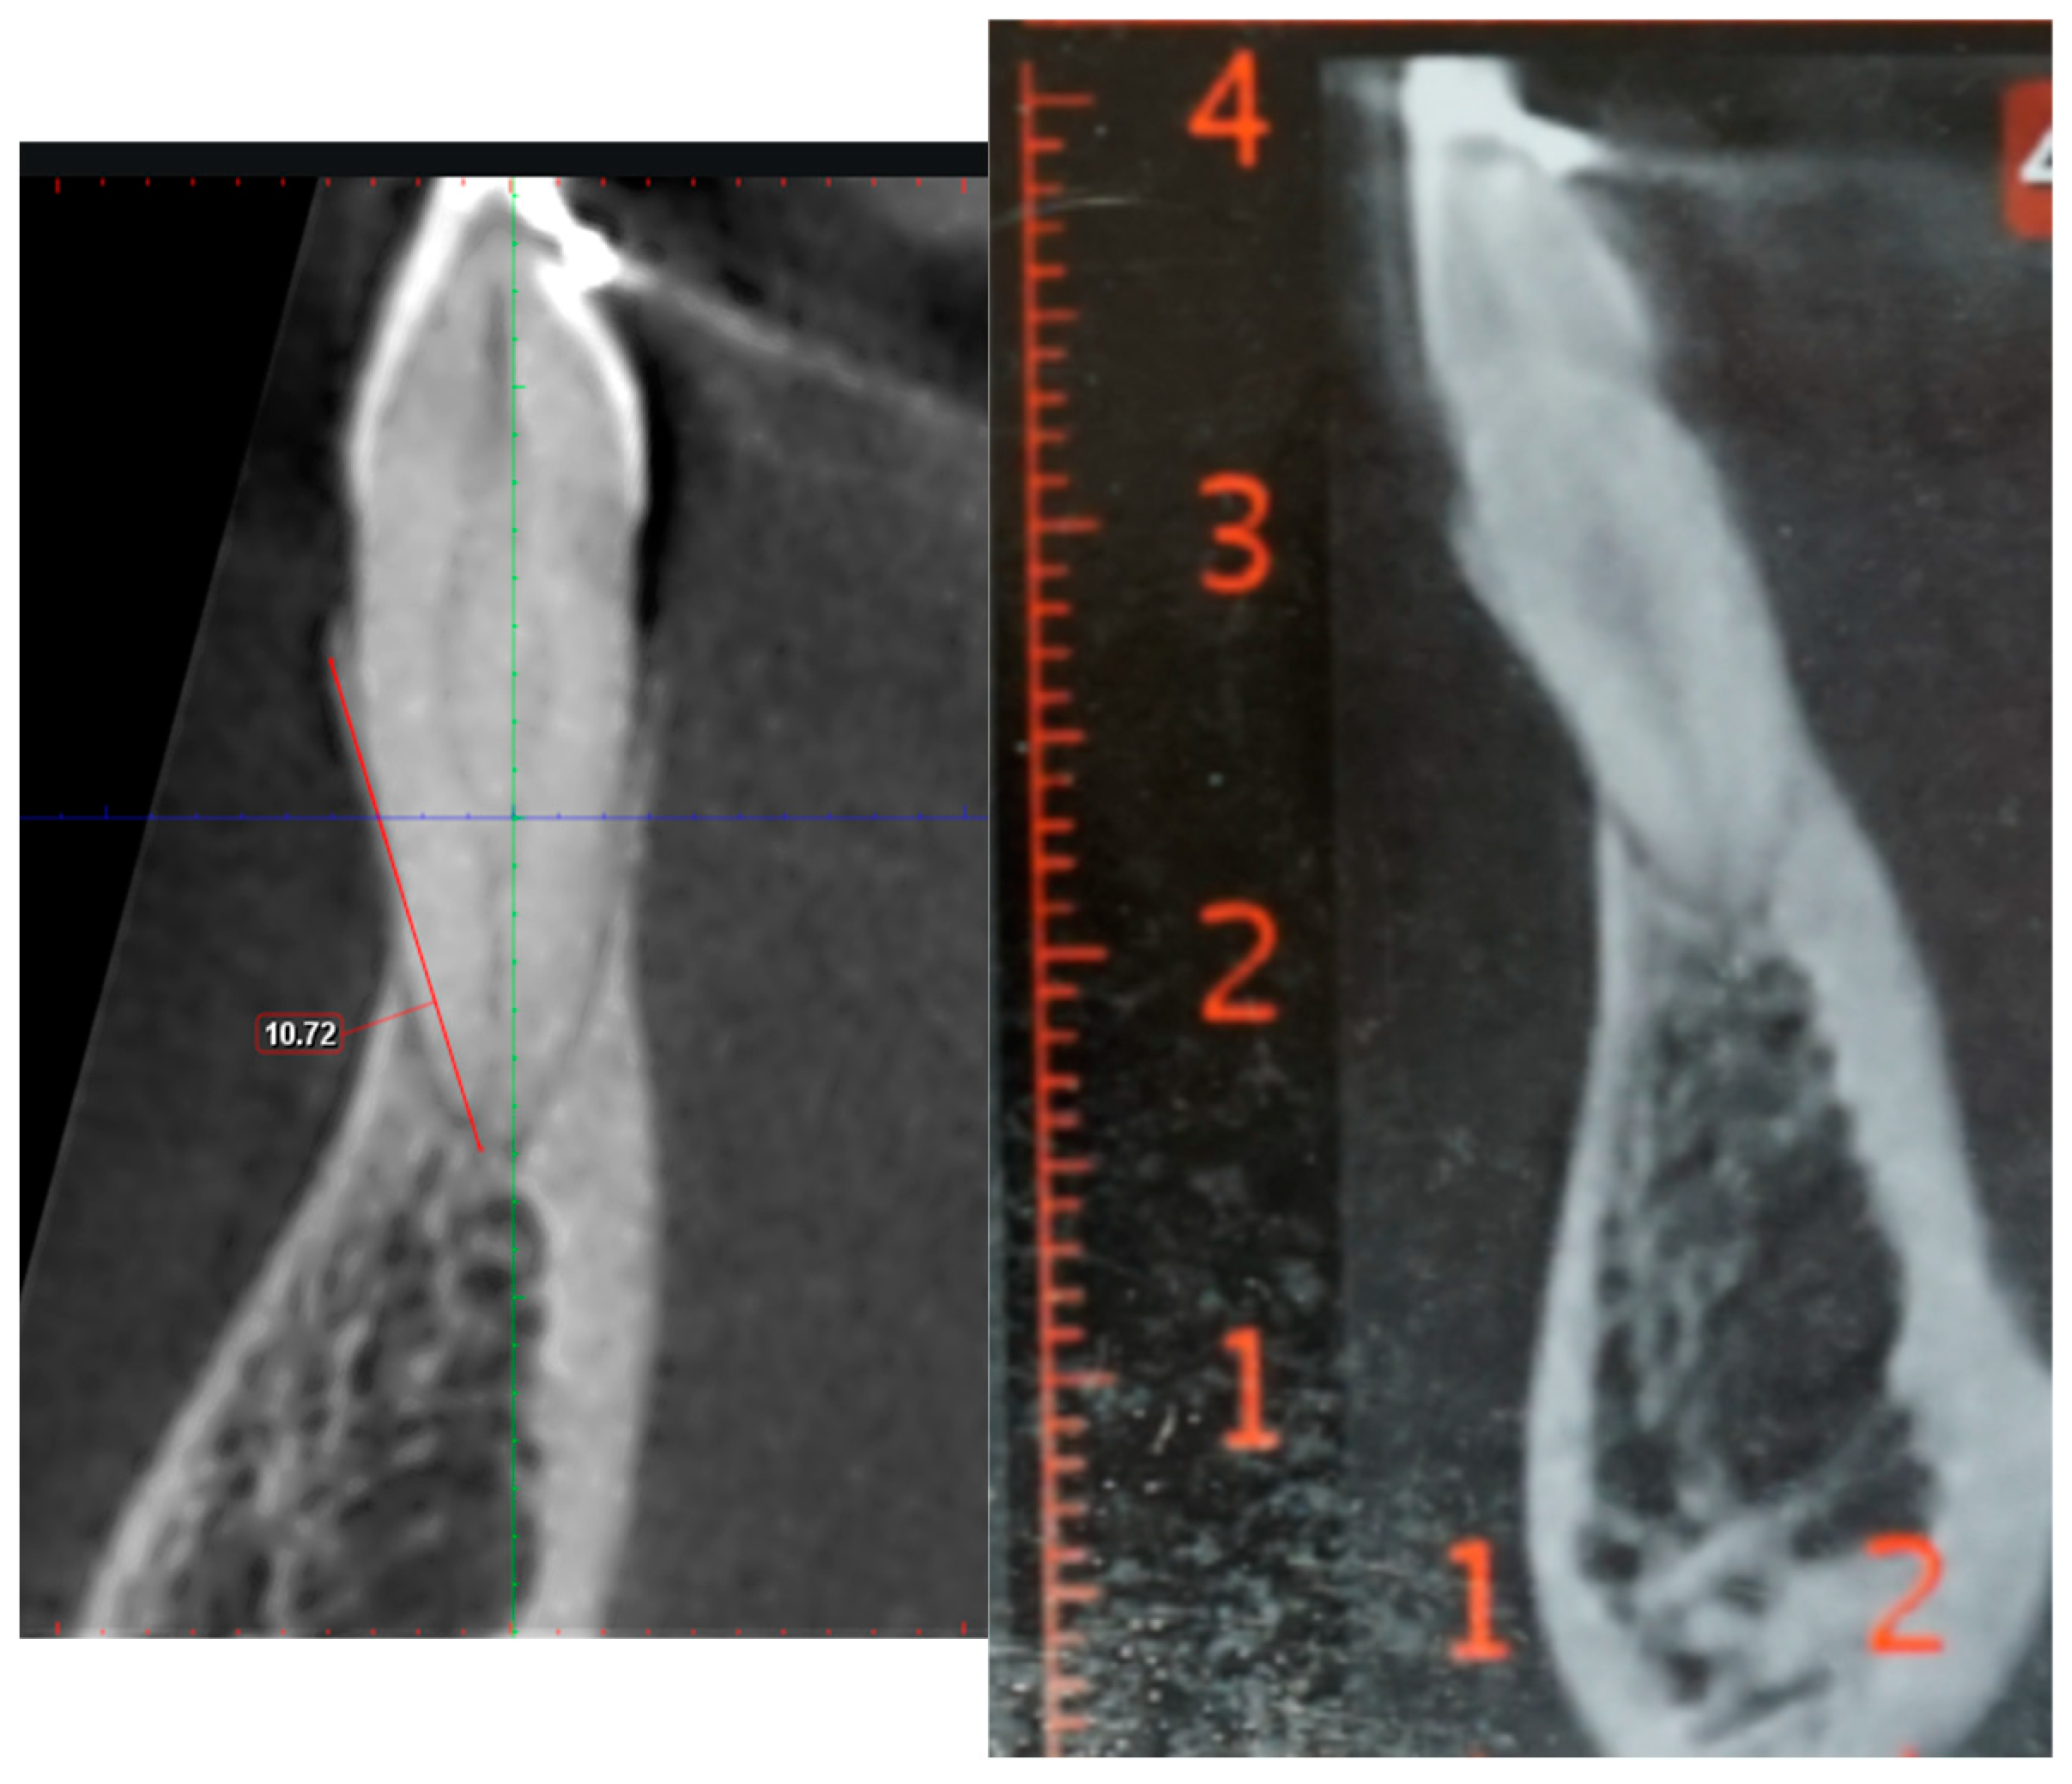

The observers evaluated the selected CBCT scans twice: first by analyzing the original Digital Imaging and Communications in Medicine (DICOM) files via Planmeca Romexis Viewer software version 6.4.7 (Helsinki, Finland) and then, one month later, by assessing printed PDF reports derived from the same scans. During both evaluations, the observers measured the diagonal distance in millimeters from the root apex of a designated tooth to the most coronal and buccal aspect of the alveolar bone (as illustrated in Figure 1). For the DICOM data, the measurements were made via a built-in software ruler, whereas for the PDF reports, a standard hand ruler was used. In cases where either the root apex or the buccal bone plate tip was not clearly visible, the measurement was categorized as “missing”.

Figure 1.

The buccal bone heights in the 3D DICOM and the PDF are similar.

The observed variability in the data was also notable, with standard deviation values ranging between −2.86 mm and 3.51 mm. This range indicates that in specific samples, the actual difference in measurements could be as high as 7 mm. This discrepancy is clinically significant even in patients with healthy periodontal support, as it could result in misjudgment of the alveolar bone condition. To illustrate this point, Figure 1 highlights a case where the measurements from the DICOM and PDF files were relatively similar, showing minimal differences. In contrast, Figure 2 shows a case where the discrepancy between the two modalities reached a mean difference of 9 mm. Differences of this magnitude could drastically alter the treatment plan, potentially leading to over- or underestimation of periodontal health and bone support.